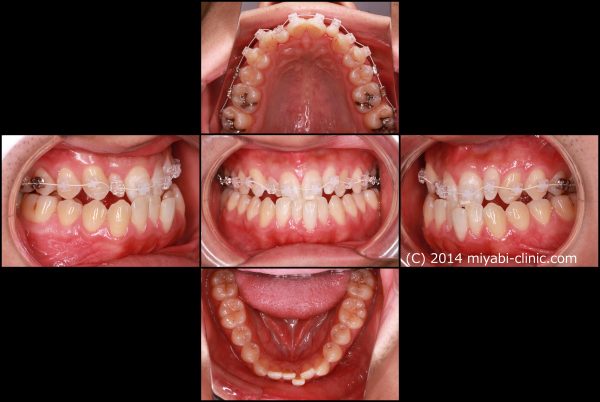

ワイヤーとゴムを使用した治療により反対咬合を修正しました。

2017年の6月27日にスタートして 2018年の10月2日に 終了 しました。

治療期間 16か月

受け口は すっかりと治り 口もとも大きく変わりました

「自信がなさそうな 表情だった息子が自信をつけて すっかりと 男前になった」と

お母さまは とても喜んで頂けました。

16歳 男性 叢生を伴う反対咬合 治療期間16か月 唇側矯正装置(ホワイトワイヤー)拡大装置(ワイヤー型)非抜歯治療 参考治療費 約65万円 (精密検査から終了まで) 矯正治療に伴う副作用の歯肉退縮、知覚過敏、歯根吸収などは認められませんでした。